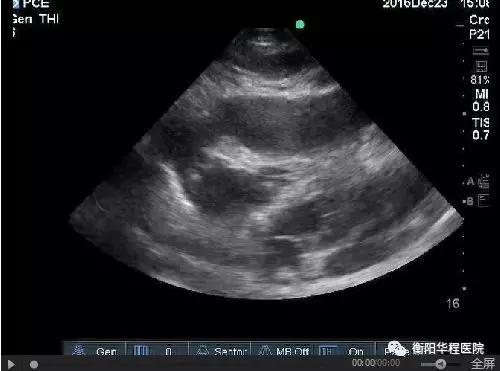

圖1  劍突下切面見大量心包積液伴右心室塌陷